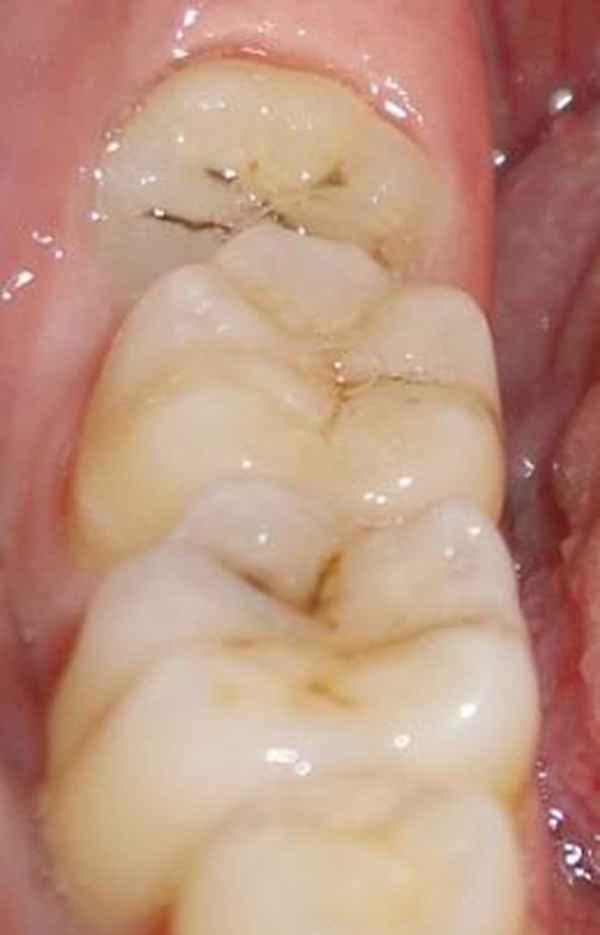

1、智齿有蛀牙的情况:

如果智齿出现了蛀牙的情况的话,是要马上拔除的,智齿是一个比较容易发生蛀牙的部位,主要是其位置比较靠近里面,我们平时刷牙很难清洁到的缘故,所以容易产生蛀牙。